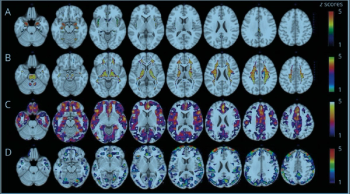

Image analysis method allows clinicians to more accurately see changes in the brains of patients with schizophrenia based on specific therapies.